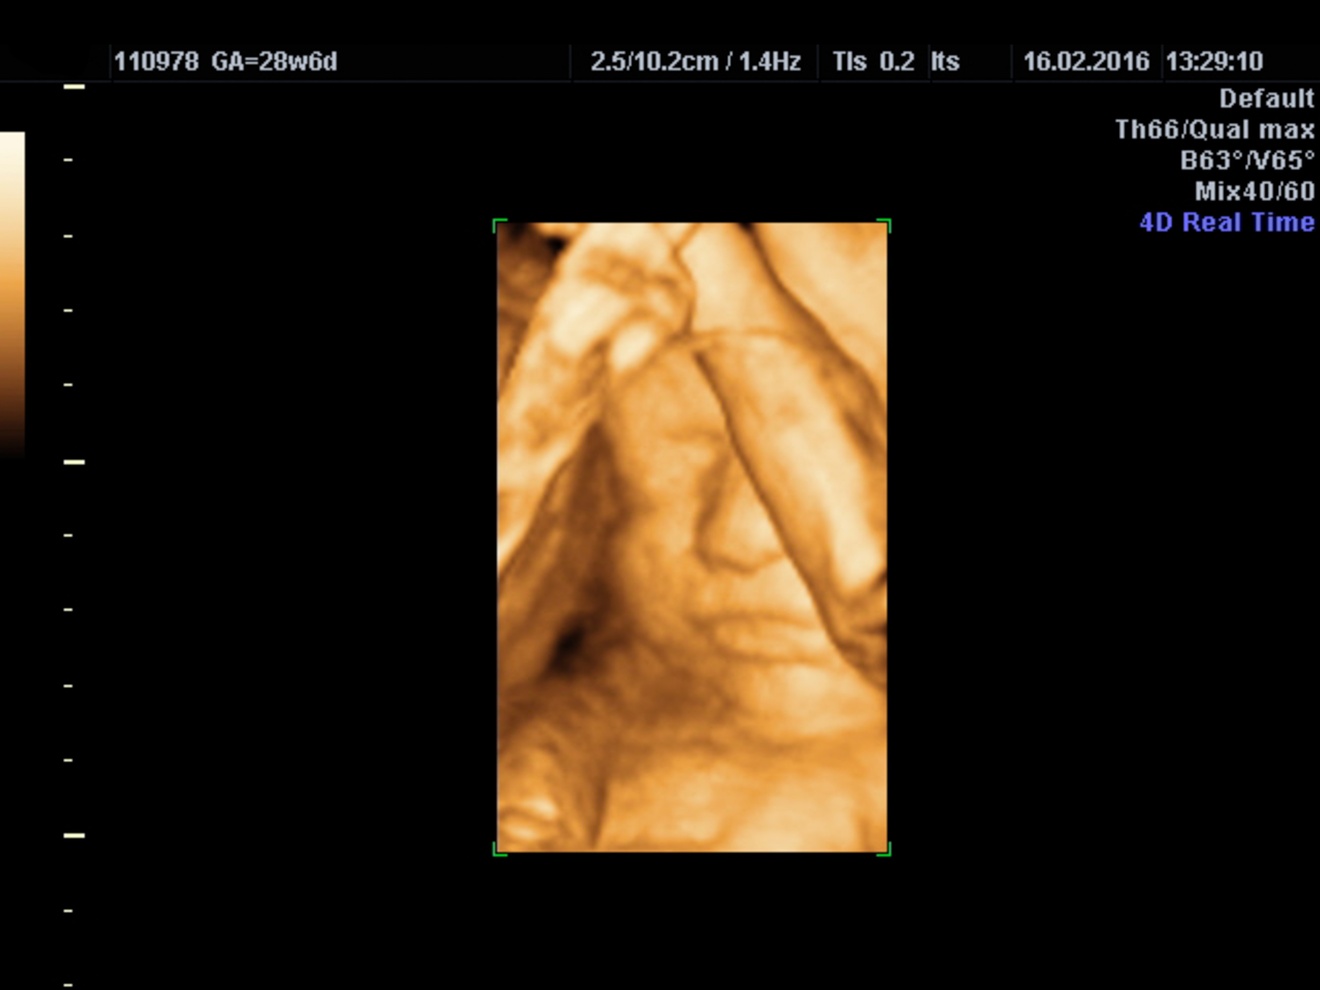

4Dエコーは、赤ちゃんの動きや表情をリアルタイムで動画として見ることができ、妊婦さんやご家族にとって感動的な体験を提供します。

4Dエコーは、3Dエコーに時間(動き)を加えた、胎児の様子をリアルタイムで動画として見ることができる技術です。従来の2Dエコーでは平面的な白黒の画像しか見られませんが、3Dエコーでは立体的な画像が得られます。4Dエコーはその3Dの画像に動きが加わることで、まるでお腹の中の赤ちゃんが動いているように感じることができます。

⬇️ 3D